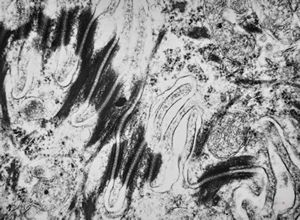

F,68y. | APUD carcinoma